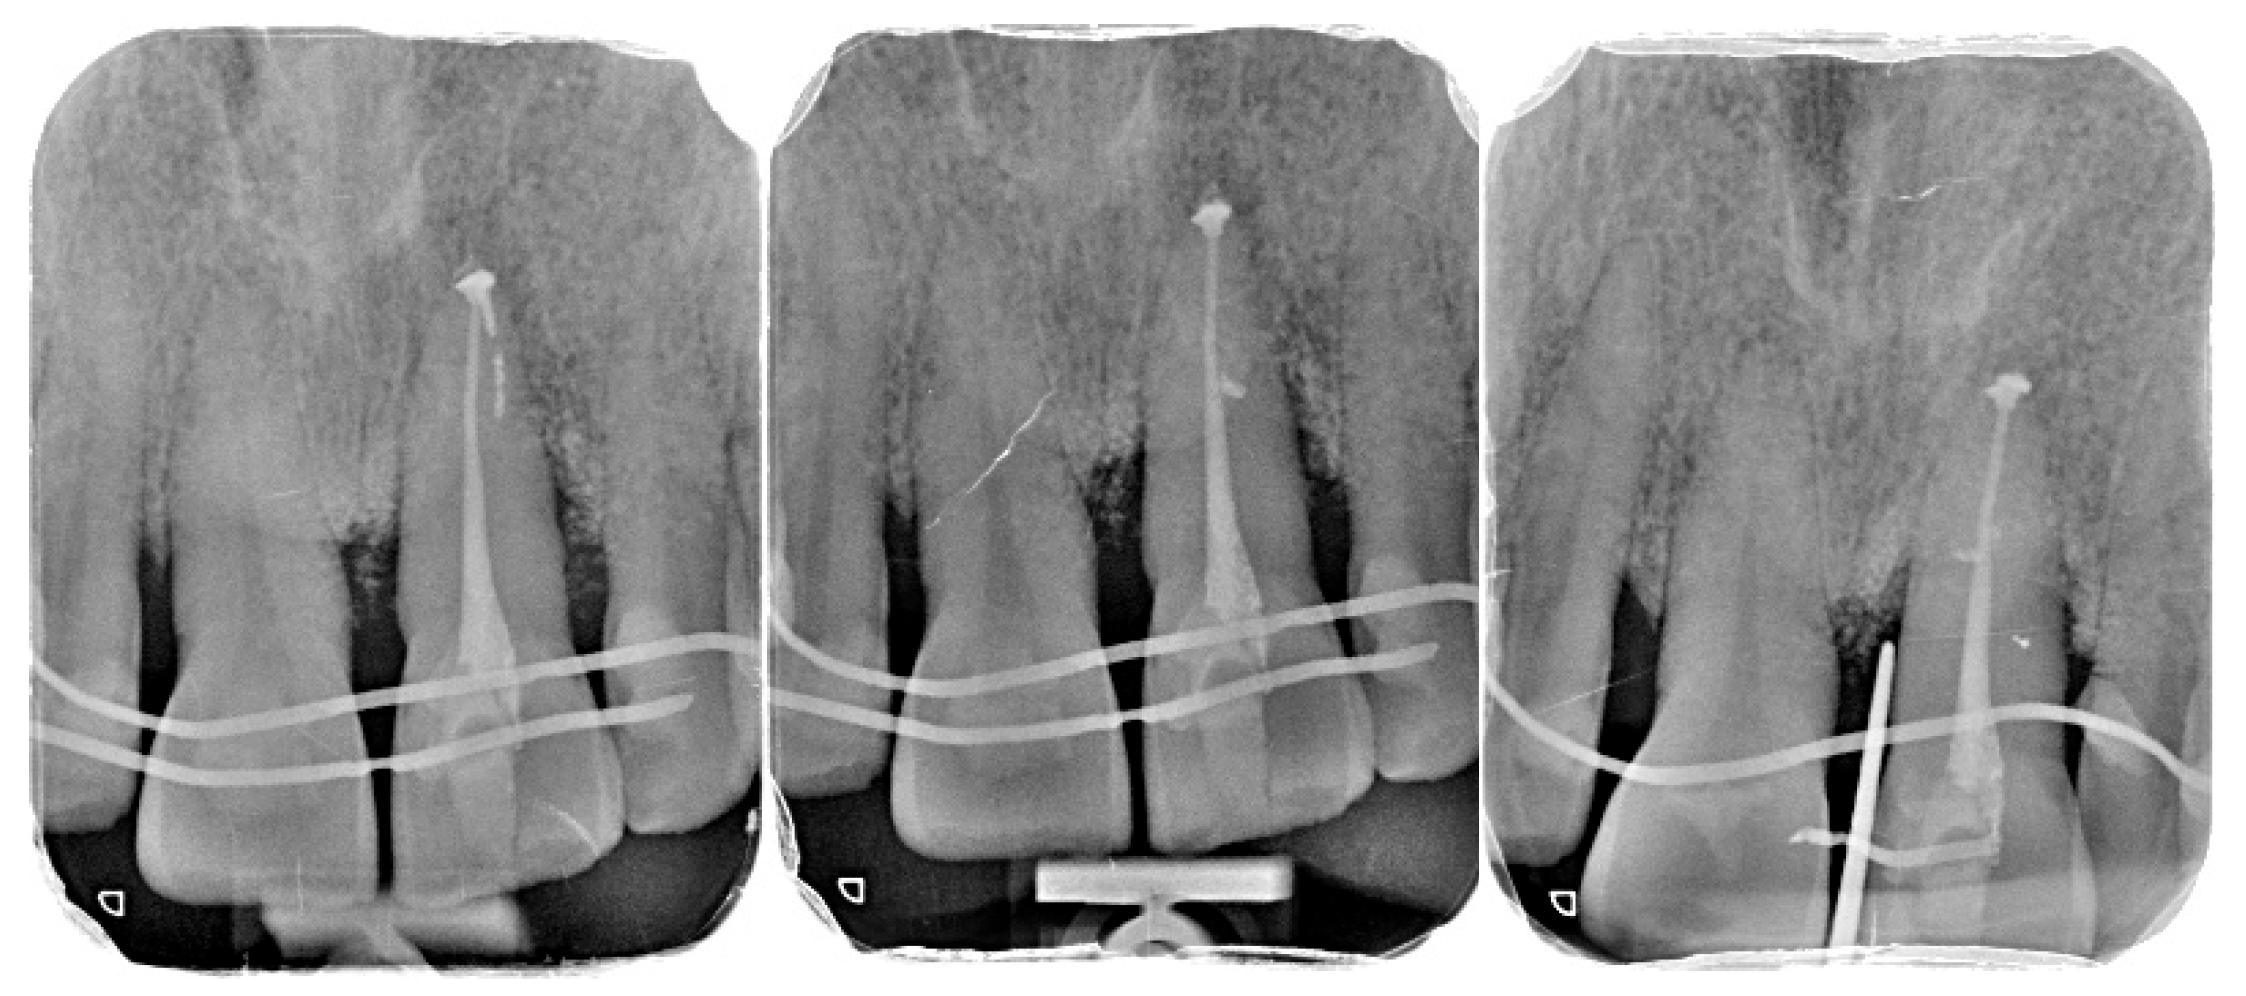

- Preparation of the recipient socket: After curettage of granulation tissue from the original socket, the CAD/CAM surgical guide was positioned. A guided osteotomy was performed using the implant-type drills from the C3D Cambados guided surgery kit, following the virtual plan. A biologic drilling protocol without irrigation was used to preserve autologous bone chips in the osteotomy walls. These chips were collected and later used as graft material. Drill sequence, diameters, and depth calibration followed the manufacturer’s recommendations and the digital plan, maintaining a stable trajectory and preserving palatal bone for primary stability.

- Verification with the 3D-printed replica: The printed tooth replica was inserted into the prepared socket to confirm angulation and depth prior to replantation of the original tooth.

- Extraoral root-end management: During the extraoral phase, apicoectomy was performed, and a retrograde cavity was prepared and sealed with a bioceramic material (Biodentine®, Septodont, Saint-Maur-des-Fossés, France) to provide an apical barrier and reduce contamination risk.

- Replantation and splinting: The original tooth was replanted into the digitally prepared socket, achieving primary stability by adapting to the prepared walls and remaining palatal bone. A semi-rigid splint was placed using fibre-reinforced composite bonded to adjacent teeth, planned for a 4-month period.